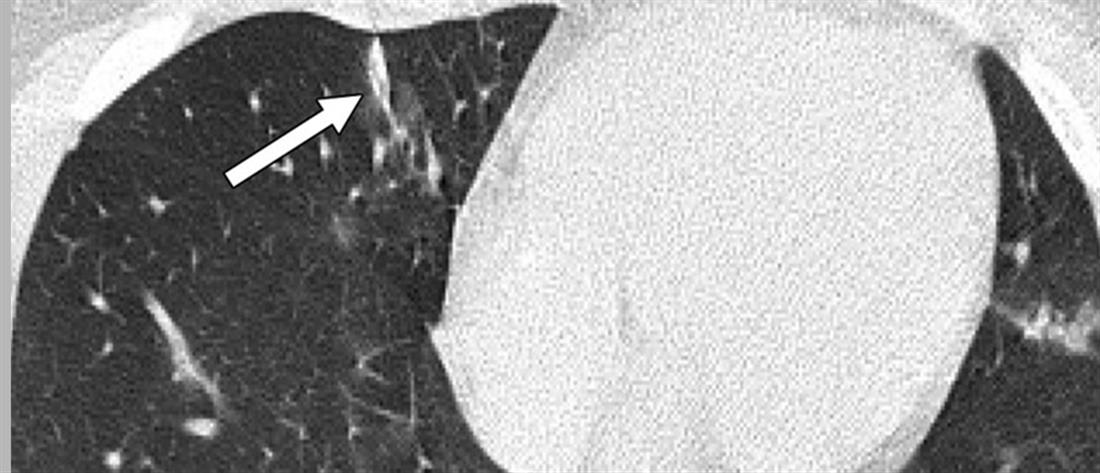

Το μήνυμα συνοδεύεται από αξονικές τομογραφίες νέων, κάτω των 18 ετών, που νόσησαν και δείχνουν τις σοβαρές βλάβες που υπέστησαν στους πνεύμονες.

«Μία εικόνα χίλιες λέξεις.

Αξονικές τομογραφίες νέων κάτω από 18 έτη με COVID-19 (18 ετών, 15 ετών, 14 ετών και 8 ετών). Κανένας ασθενής δεν είχε υποκείμενα νοσήματα ή ανοσοκαταστολή. Οι ασθενείς δεν χρειάστηκαν συμπληρωματικό οξυγόνο, διασωλήνωση ή ΜΕΘ. Πρόκειται για απλά-κοινά περιστατικά COVID-19.

Ωστόσο έχουν πολύ “εντυπωσιακές” βλάβες και είναι άγνωστο τι θα προκαλέσουν αυτές οι βλάβες σε βάθος χρόνου.